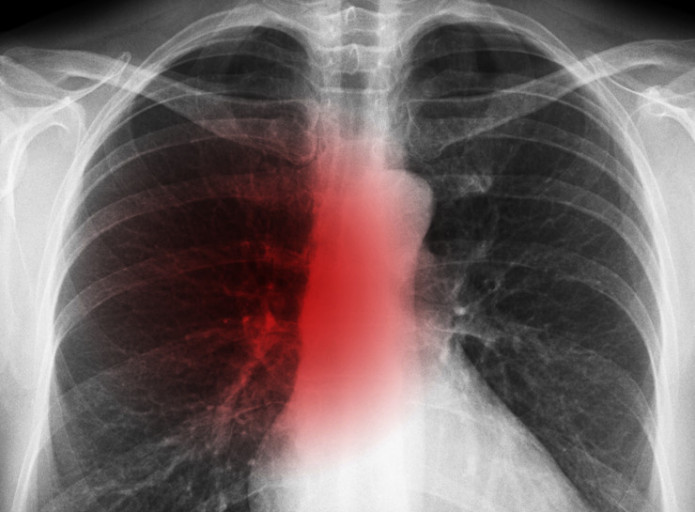

오늘은 우리 몸의 호흡을 책임지는 폐에 대해 이야기하려 합니다. 특히, 폐에 발생하는 악성 종양인 폐암의 초기 증상에 대해 자세히 알아보려 합니다.

폐암 초기증상 폐암은 초기 증상이 감기나 다른 호흡기 질환과 비슷해 간과하기 쉽습니다. 하지만 조기 발견이 치료에 매우 중요하기 때문에, 미묘한 변화라도 놓치지 않는 것이 중요합니다. 지금부터 폐암의 주요 초기 증상들을 꼼꼼히 살펴보고, 건강을 지키는 첫걸음을 함께 시작해 볼까요?

폐암 초기에는 특별한 증상이 없는 경우가 많지만, 암이 진행되면서 다양한 신호를 보낼 수 있습니다. 다음은 폐암 환자들이 흔히 경험하는 10가지 주요 초기 증상입니다.